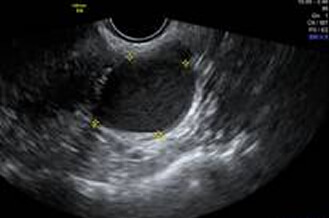

Normal uterus